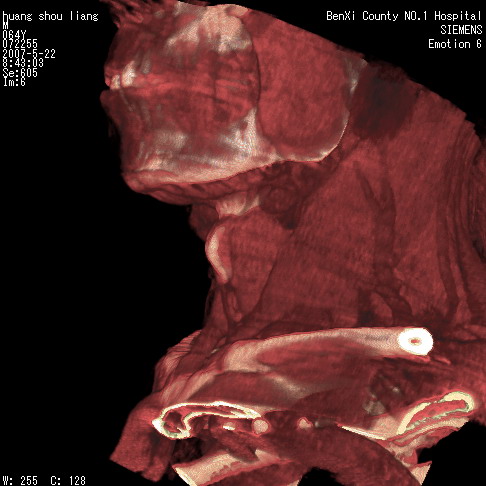

男性,64岁。颈部包块8年。最近增大。

对不起大家,可能是片子发太多有点乱,正常腮腺在下颌角的外侧,颌下腺在下颌体的中部内侧,本例在下颌角内侧偏下,和腺体一点关系都没有,从vrt和mpr上可以很明显看出来,再者肿块是好多粘连在一块的,大家在仔细看看,左侧可能也是吧,我还是考虑为肿大的淋巴结融合在一块,但性质??????

多考虑颌下腺混合瘤恶变,建议进一步检查,另外楼主重建图像很漂亮。

大家好,病理结果出来了,如大家所说,颌下腺混合瘤。